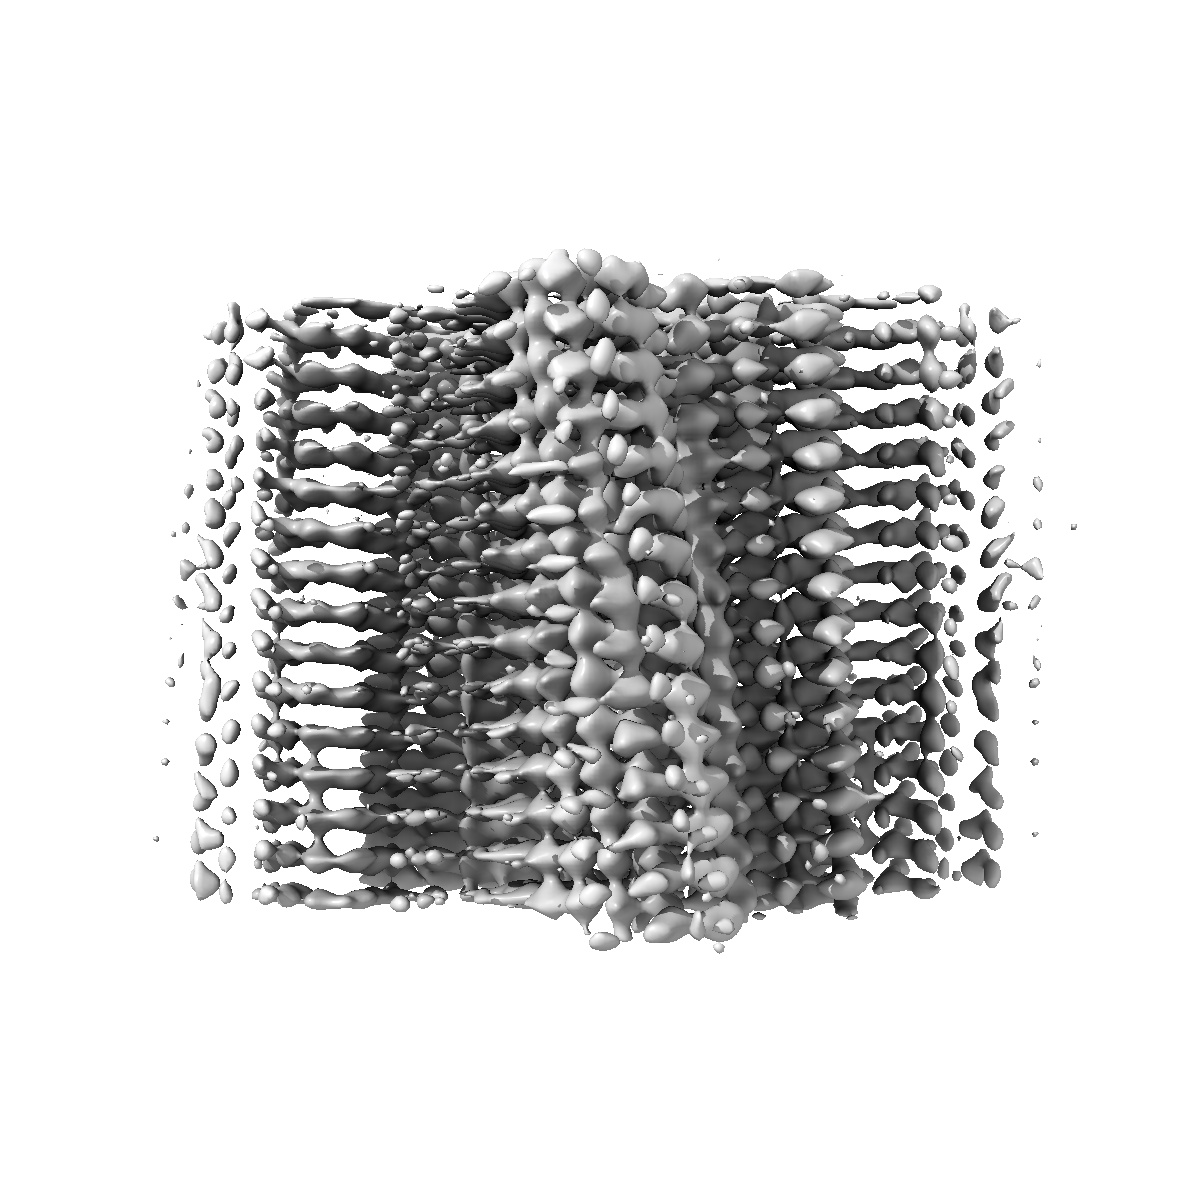

Structure of amplified aSyn filament by using seed amplification assay (SAA) from MSA patient CSF.

Helical reconstruction3.9 Å

Sample: Alpha-synuclein protein filament

Seed amplification of MSA alpha-synuclein aggregates preserves the biological and structural properties of brain-derived aggregates.